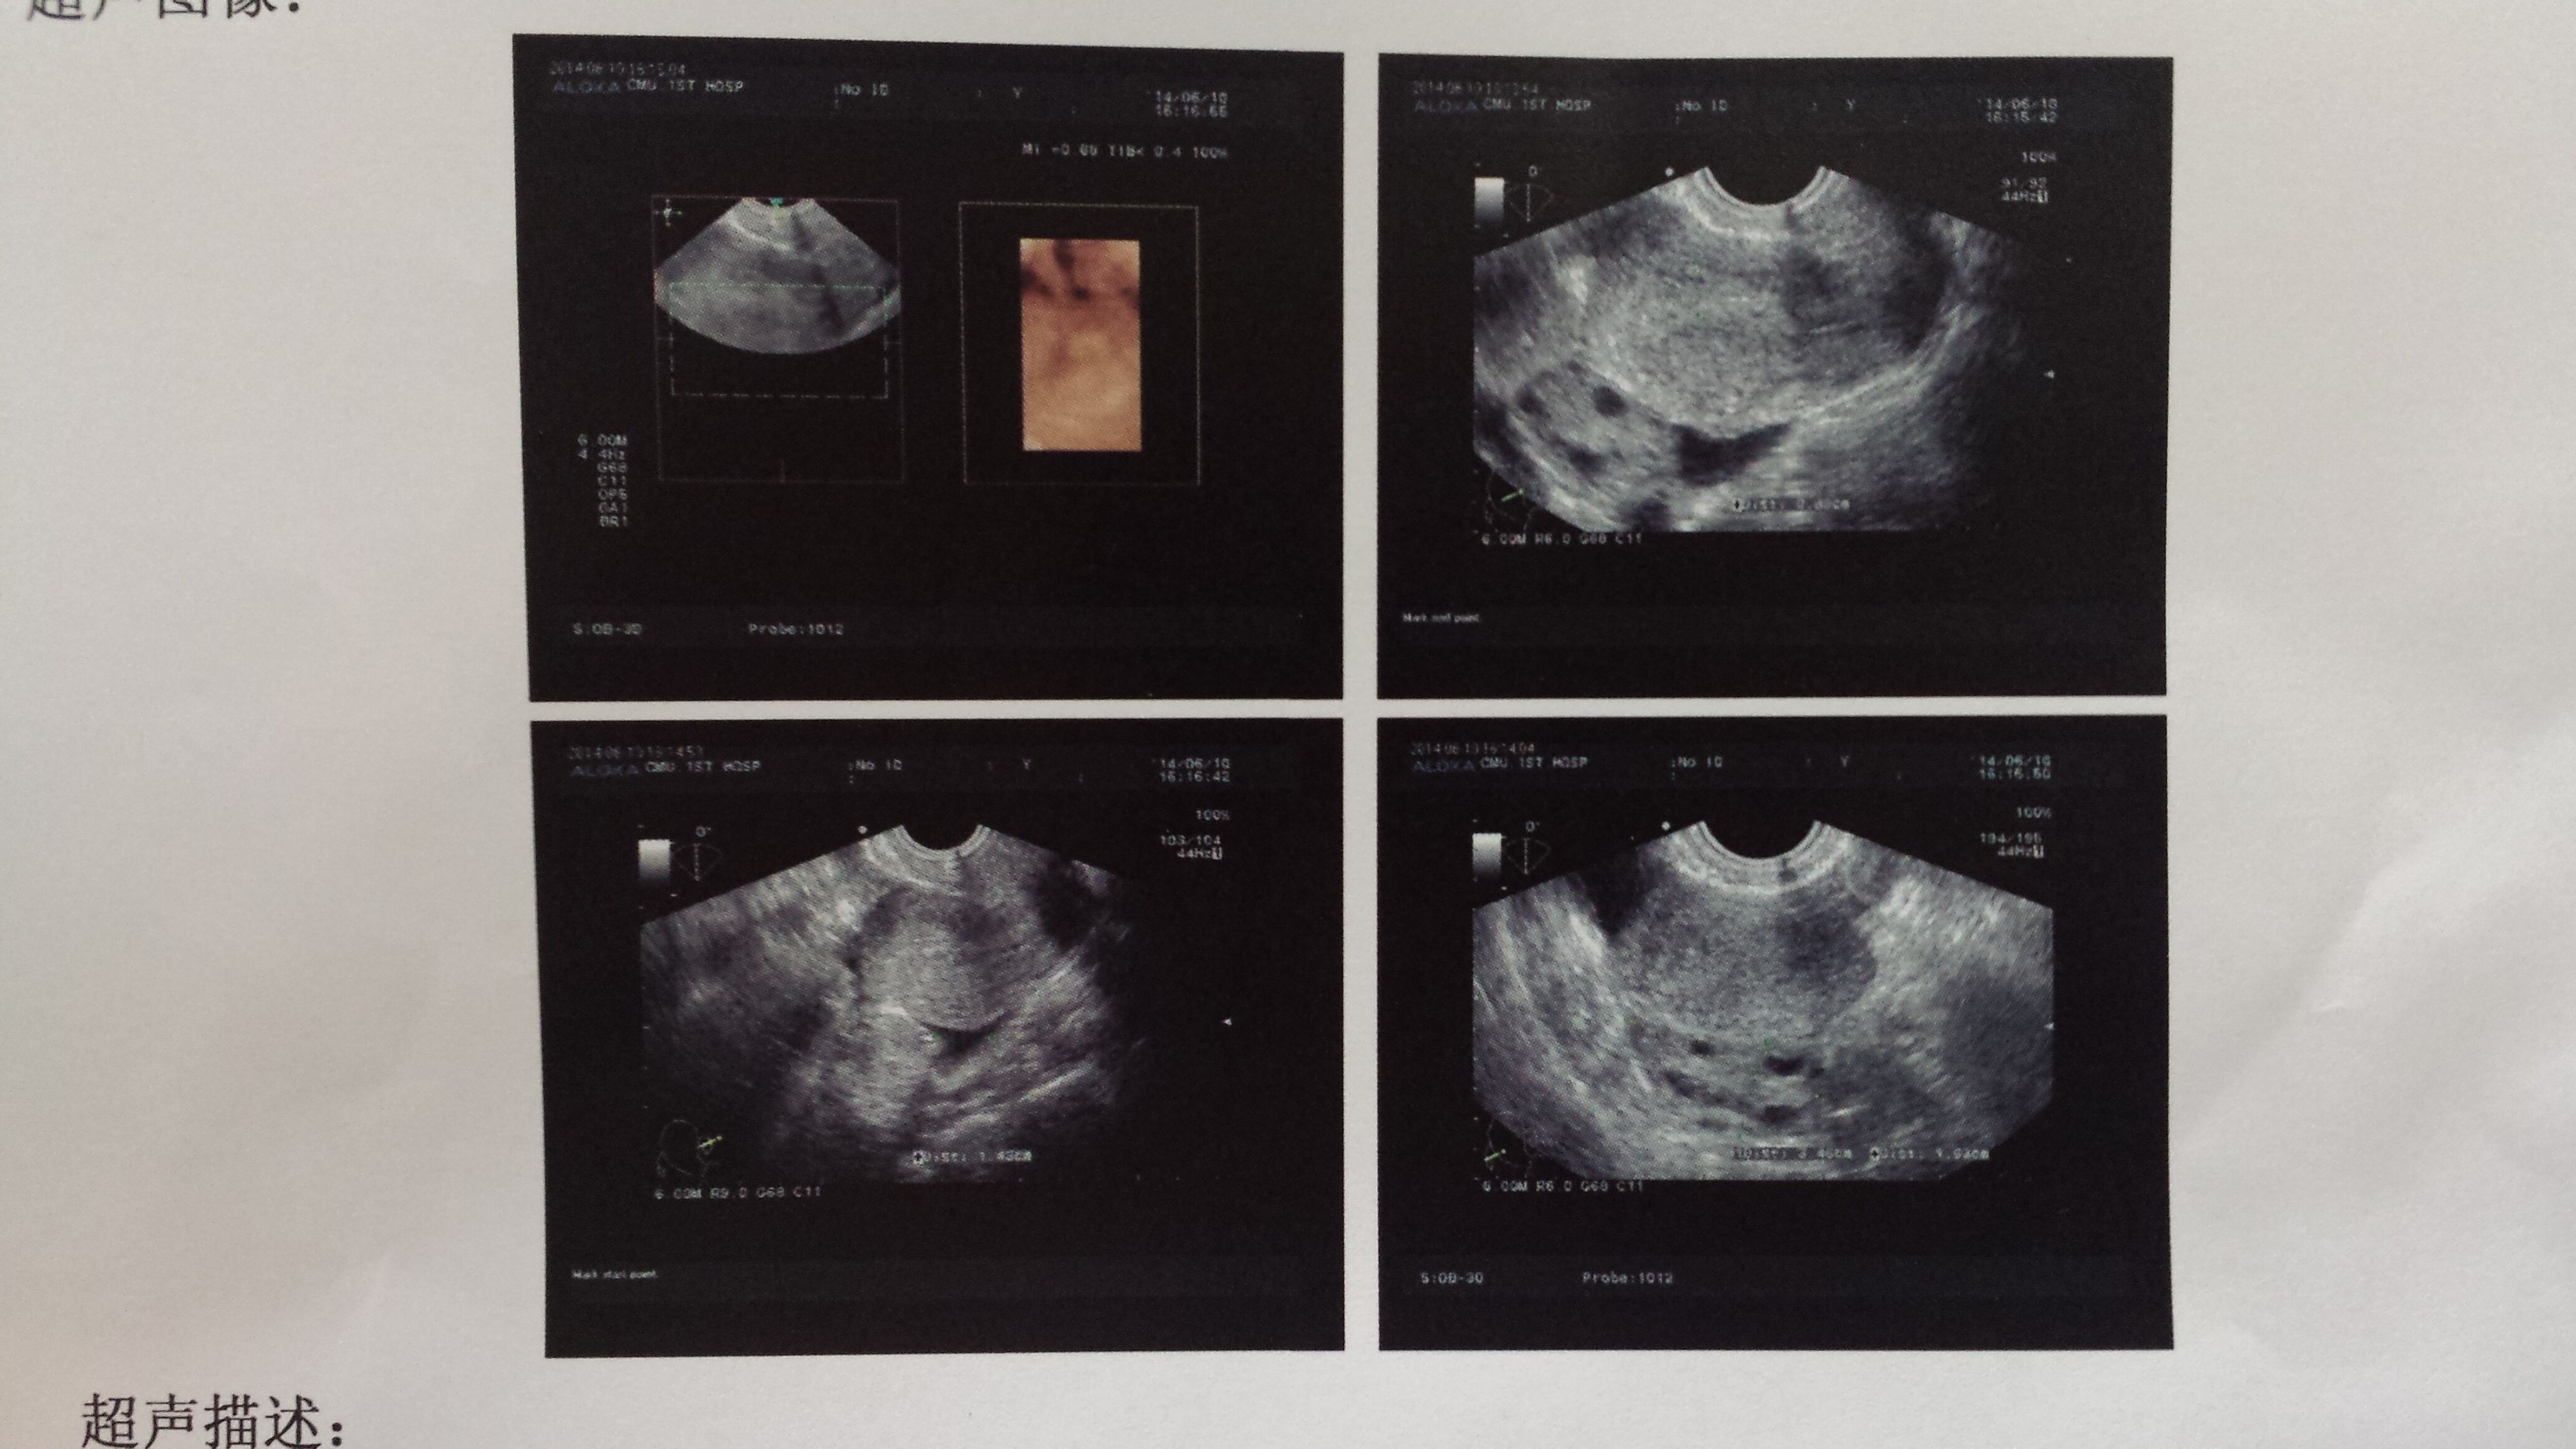

我做完人流后几个月了,久站久坐走路走多了小肚子里面酸疼,去医院检查说盆腔积液1.4cm,下面有彩超

的图片